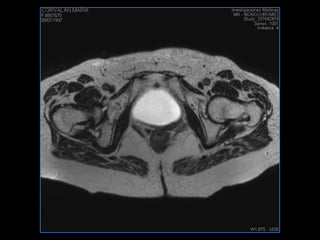

PROTOCOLO pelvis SAG T2, Y FAT SAT (FINOS) AXIAL T1  AX FAT SAT CON   GADOLINIO :  AX T1 Y COR T1 SAT: NO  FASE: RL THK: 3MM  COIL:  GAP: (FACTOR 1.4) 1MM FOV: 40 CM NEX:2 SINCRONIZACION RESPIRATORIA EN 3 O 4 CICLOS ALE